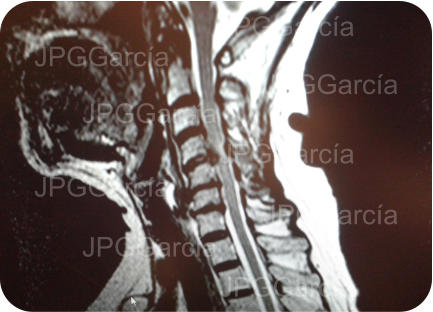

Tratamiento de hernia de disco cervical alta con compromiso medular

Tratamiento microquirúrgico de hernia extruida cervical con mielopatía